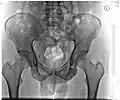

Röntgenbild eines Beckens (Mann, 46 Jahre) -

Geschlechtsunterschiede am knöchernen Becken und Variationen

Das weibliche und männliche Becken beim Menschen unterscheiden sich deutlich. Während bei der Frau die beiden Beckenschaufeln ausladender sind und das Hüftbeinloch (Foramen obturatum) eine eher dreieckige Form hat, ist das männliche Becken hoch, schmal und eng. Auch der Beckenausgang ist beim weiblichen Becken breiter; der Winkel zwischen beiden Schambeinästen ist beim weiblichen Becken größer als 90° (Arcus pubicus), während er beim männlichen Becken nur etwa 70° (Angulus subpubicus) beträgt. In der Anatomie und der Geburtshilfe werden zur Beschreibung der Beckenform standardisierte Conjugata (Ansicht von lateral) und Diameter (Ansicht von kranial oder kaudal) verwendet.